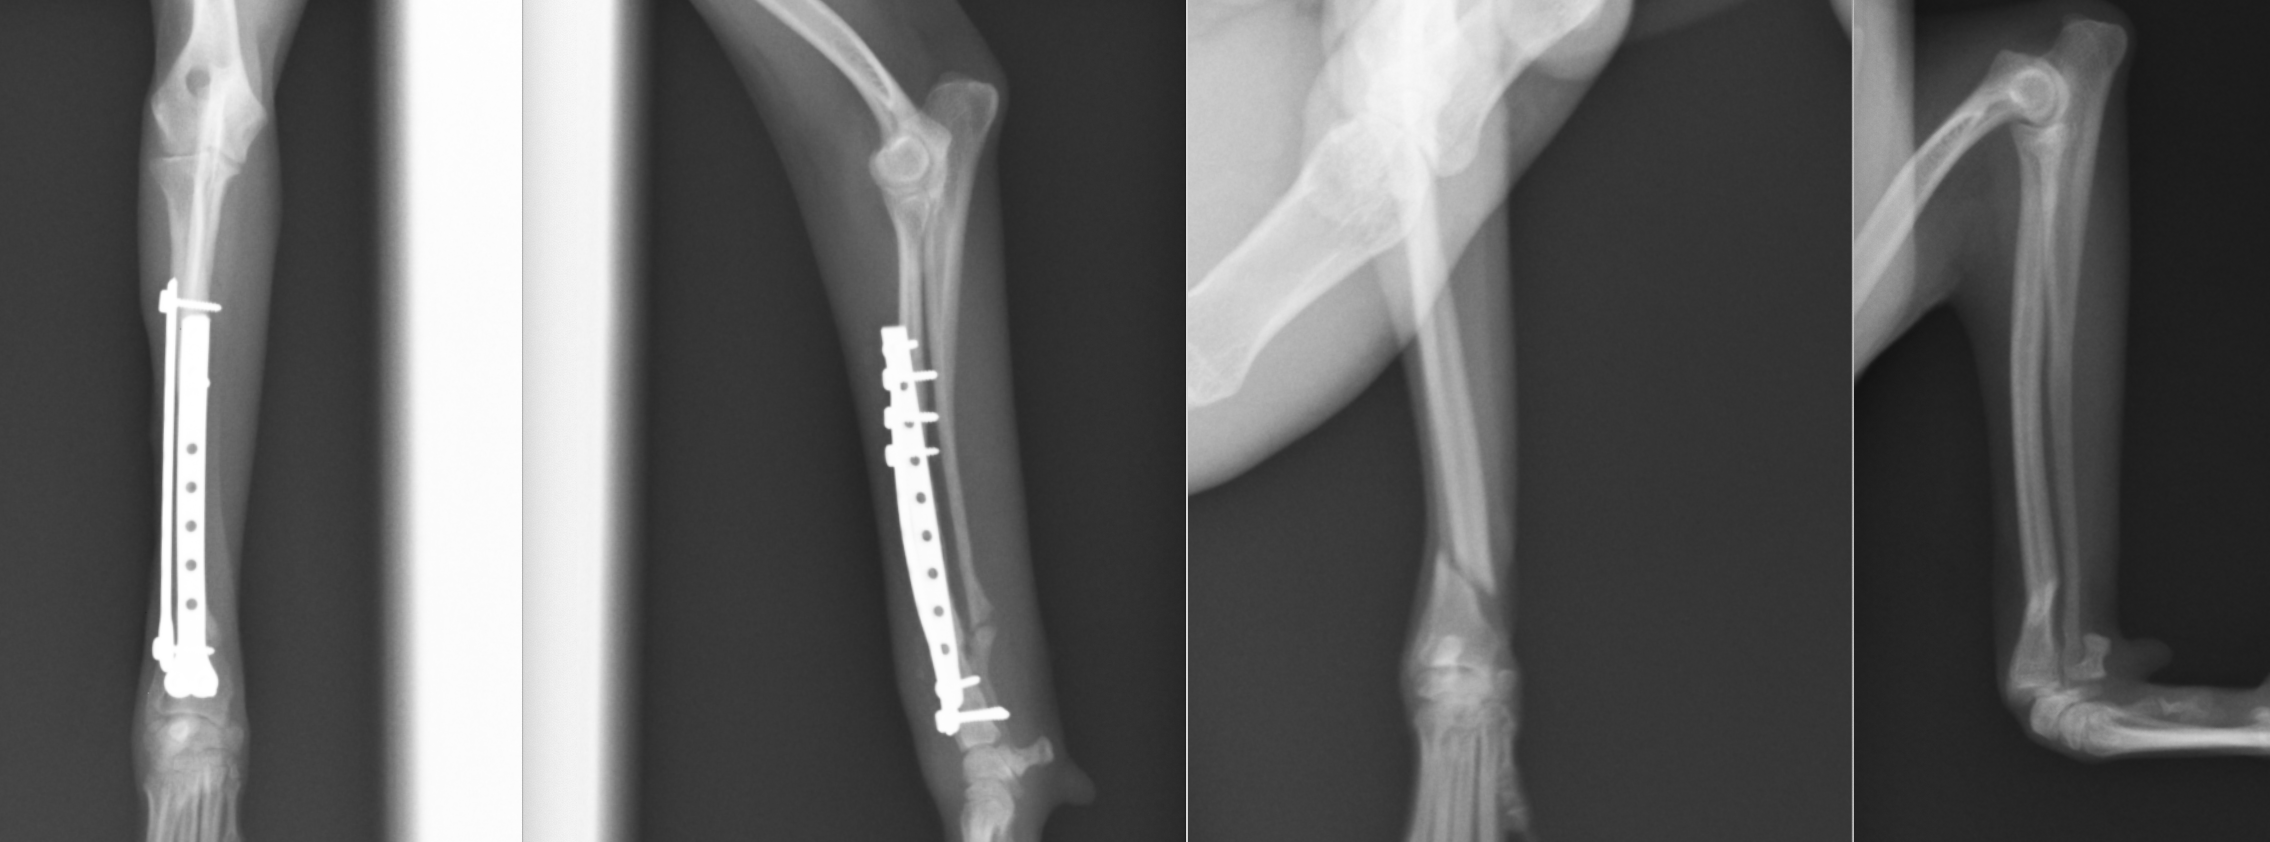

イタリアングレーハウンドの橈尺骨骨折です。2.0mmスクリューを使用しています。

トイプードル9歳の橈尺骨骨折です。1.5mmスクリューを使用しています。

トイプードル2歳の橈尺骨骨折です。1.5mmスクリューを使用しています。 上の3症例ともにやや中央寄りの先端部の橈尺骨の横骨折(遠位骨幹部橈尺骨横骨折)です。直線のプレートを使用しています。

ポメラニアン半年齢の橈骨尺骨骨折です。1.3mmの超小型スクリューを使用しました。 上の4症例はやや中央寄りの先端部の橈尺骨の横骨折(遠位骨幹部橈尺骨横骨折)です。直線のプレートを使用しています。